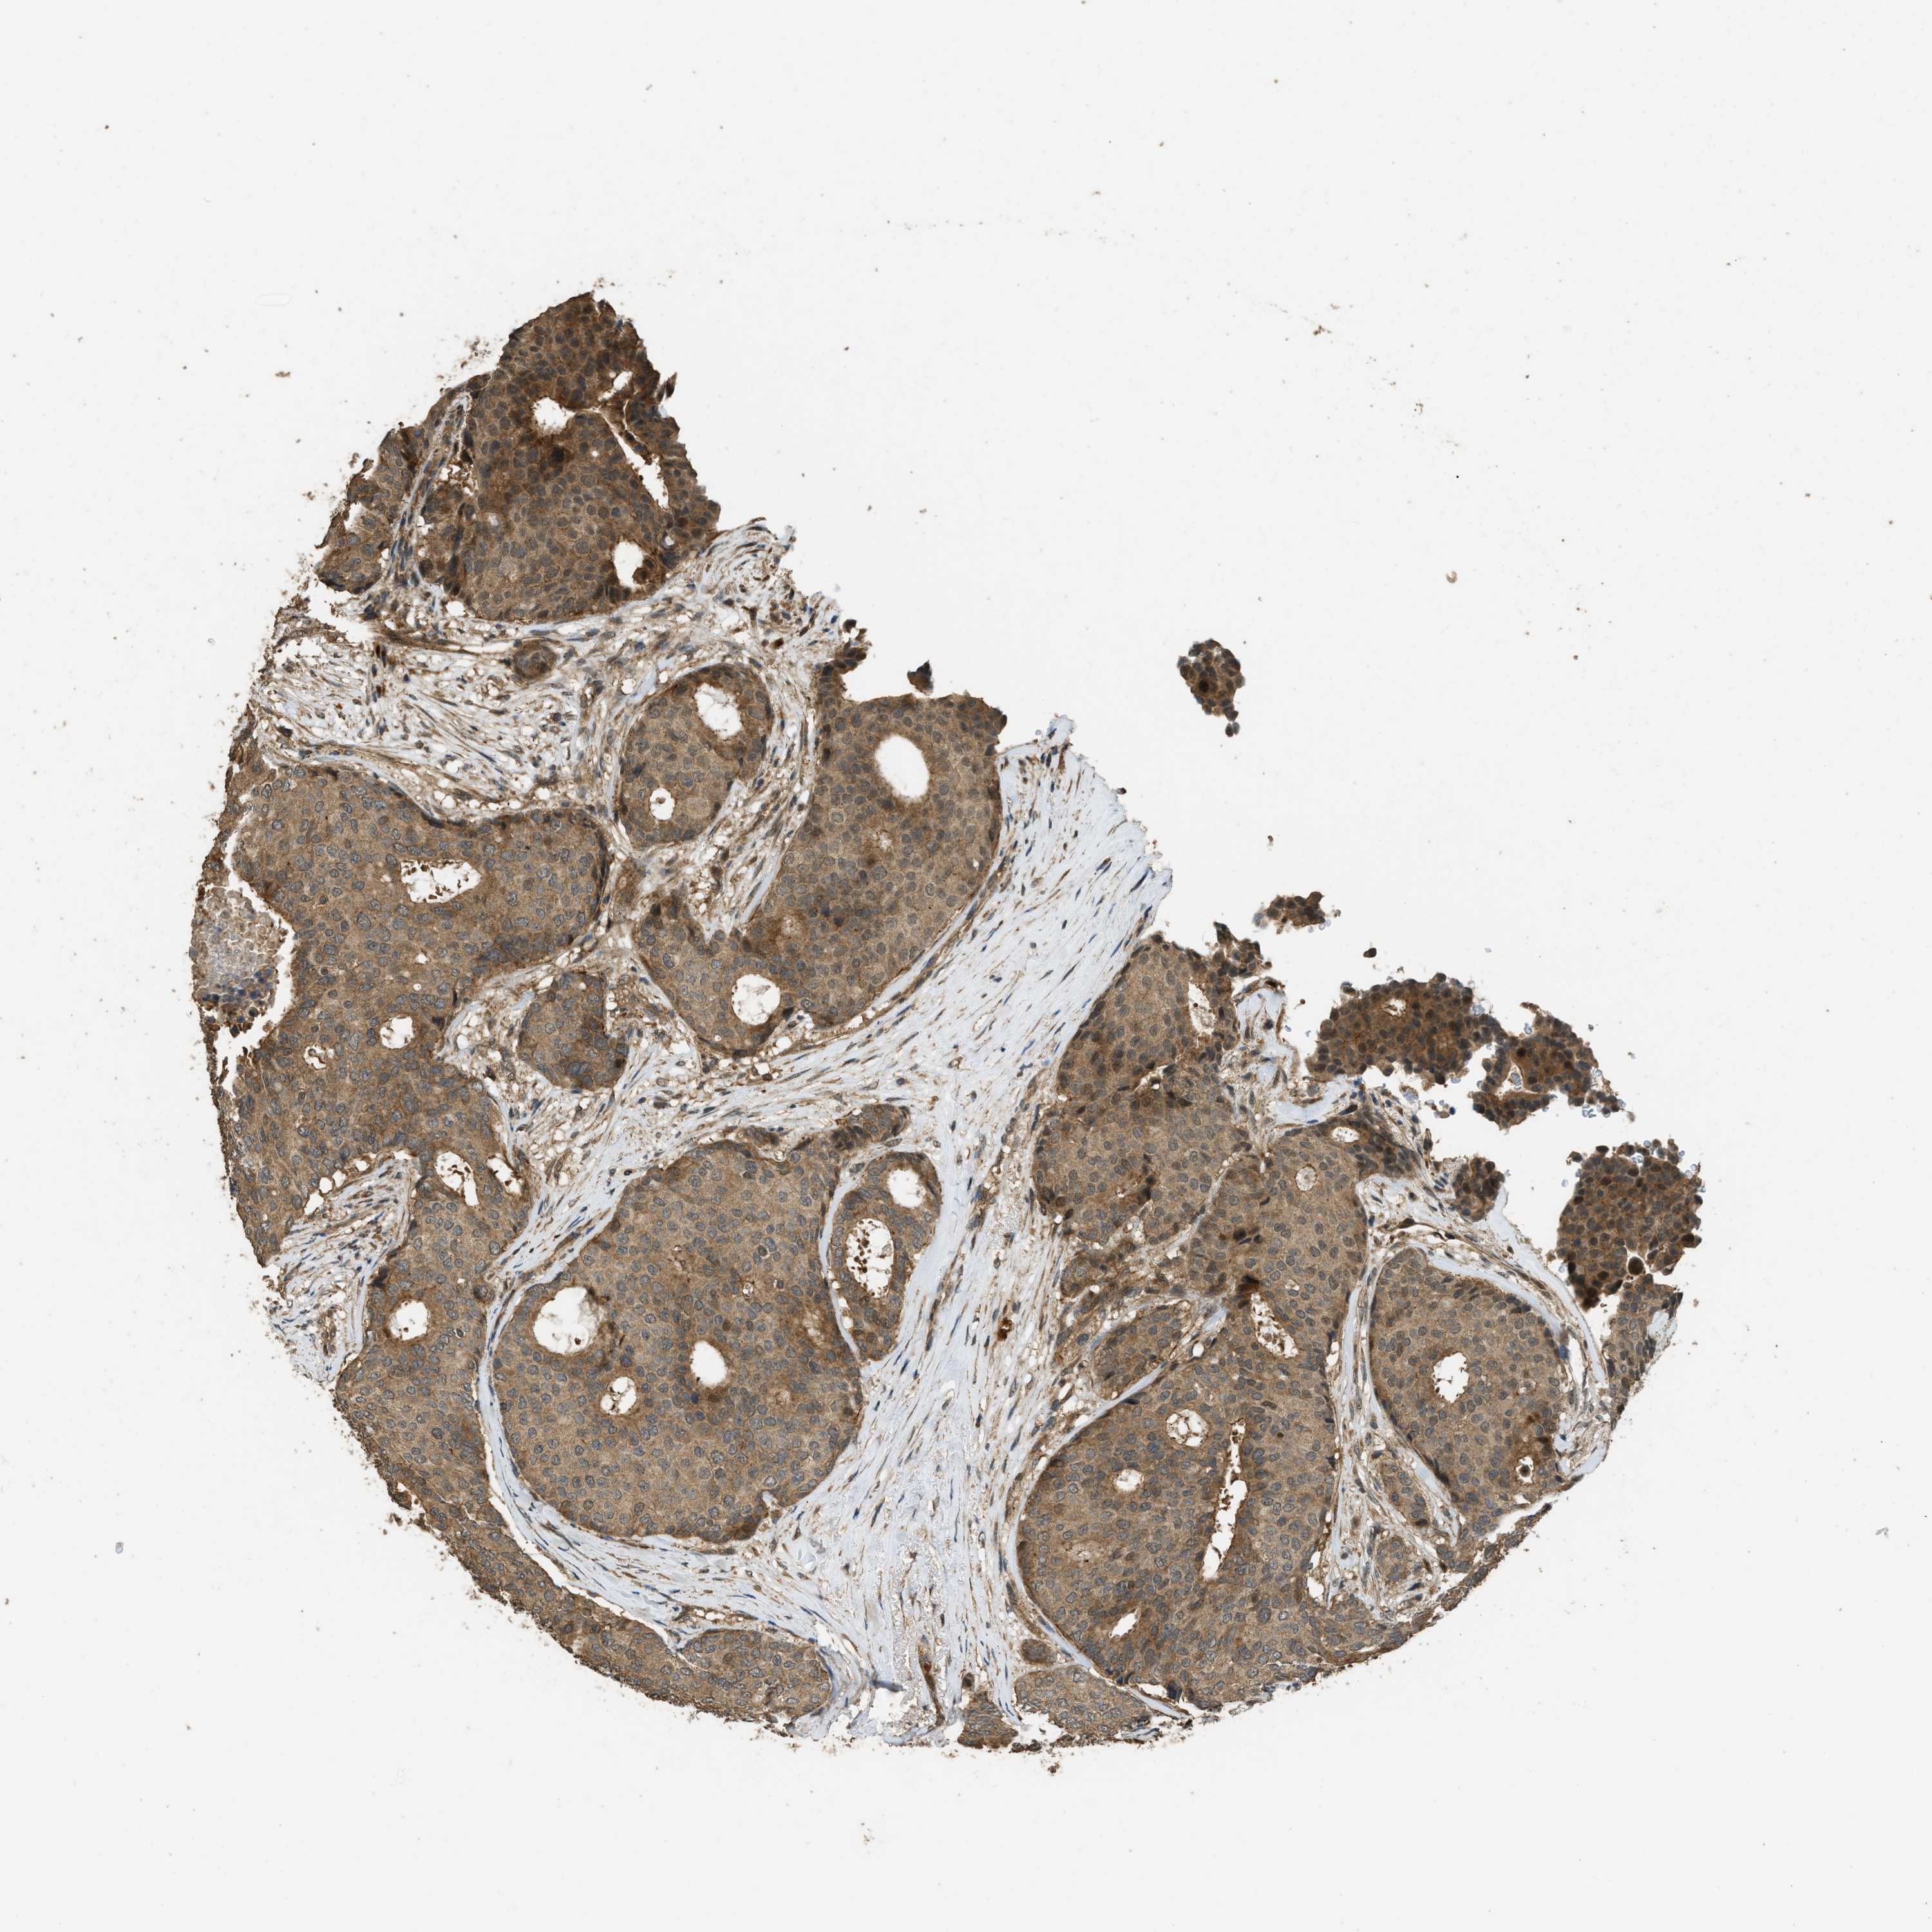

BRCA TCGA BRCA VALIDATION PROTEIN EXPRESSION

ANTIBODIES

AND

VALIDATION